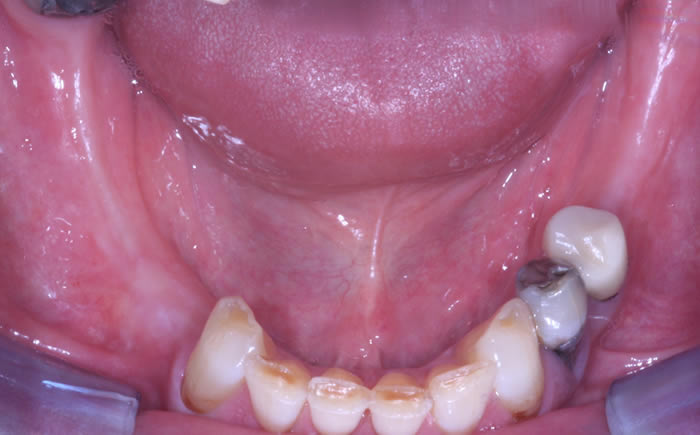

More back teeth replaced by dental implants

Case Three (2 images)

Case Four (4 images)

Case Five (4 images)

Case Six (8 images)

Case Seven (4 images)